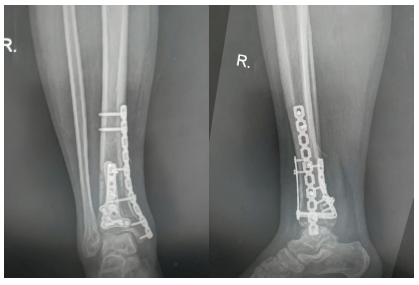

韩师傅接受了右胫骨远端粉碎性骨折切开复位内固定术+关节软骨损伤修复术。

一是恢复关节面平整:将碎裂的关节面拼回原位,这是决定日后脚踝功能的关键。

二是重建力学稳定:用钢板和螺钉将骨折端牢固固定,为骨骼愈合提供稳定的力学环境。

手术过程顺利,术后的X光片显示:骨折端实现了解剖复位,钢板螺钉位置良好,关节面恢复平整。

手术后三个月,韩师傅回医院复查。X光片显示:

内固定物无松动、无断裂;

胫骨远端骨折线已模糊,连续性骨痂形成,骨折进入临床愈合阶段;

踝关节面平整,没有出现塌陷或关节炎改变。

这个结果让医生和韩师傅都松了一口气。骨折愈合进展符合预期,为后续逐步负重和强化康复奠定了良好基础。